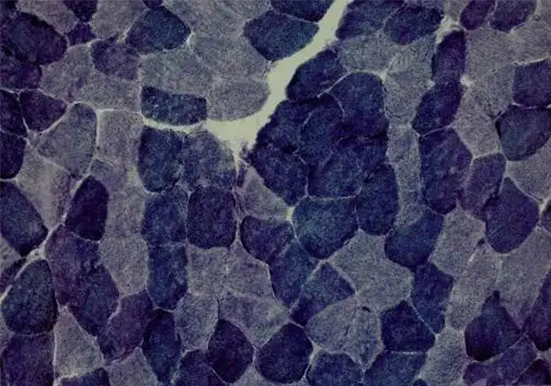

ATP 酶染色

以下是关于 ATP 酶染色的相关介绍:基本原理ATP 酶是一种水解酶,可催化 ATP 分解产生能量。在 ATP 酶染色中,常用的是钙钴法,其原理是 ATP 酶水解 ATP 为 ADP 和磷酸,磷···